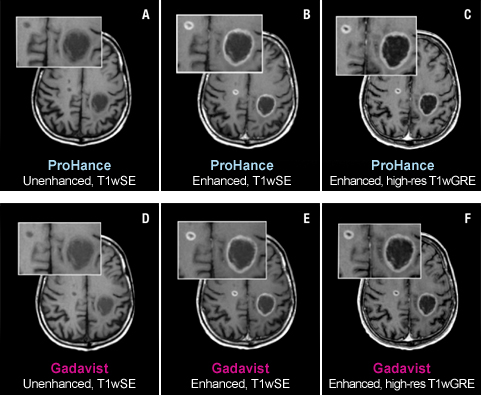

Case Studies

Case Study 1

61-year-old male with brain metastases from primary lung cancer. Two lesions clearly seen in both exams show no differences in contrast enhancement or in the morphology of lesions.1

These are representational images from reference studies. Individual results may vary. REFERENCE: 1. Maravilla K, Smith M, Vymazal J, et al. Are there differences between macrocyclic gadolinium contrast agents for brain tumor imaging? Results of a multicenter intraindividual crossover comparison of gadobutrol with gadoteridol (The TRUTH study). AJNR Am J Neuroradiol. 2015;1:14-23, doi: 10.3174/ajnr.A4154.